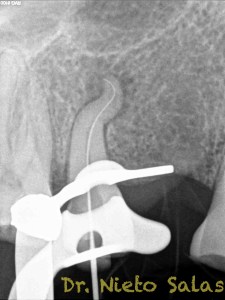

Se nos presenta en la clínica un par de casos de características similares, con lo cual las hemos tratado igual:

Ante estas situaciones, lo que no debemos es intentar llegar a la zona apical rápido, primero prepararemos el tercio medio-coronal, pero sin perder la permeabilidad del conducto con limas de muy pequeños diámetro.

Una vez que tenemos la Long de trabajo, no debemos perderla, se recomienda mucha irrigación e intentaremos que nuestras limas trabajen en una superficie lo menor posible.

Con respecto a lo puramente endodóntico, la verdad que fueron unos casos de verdadero estrés para no perder la permeabilidad ni la long de trabajo, con técnica corona-apice y con un diametro apical de 20, instrumentado solo la parte apical con limas de Mtwo , la parte coronal me ayudé de ultrasonidos. No sé, que más contarte con respecto a la conformación de los conductos.